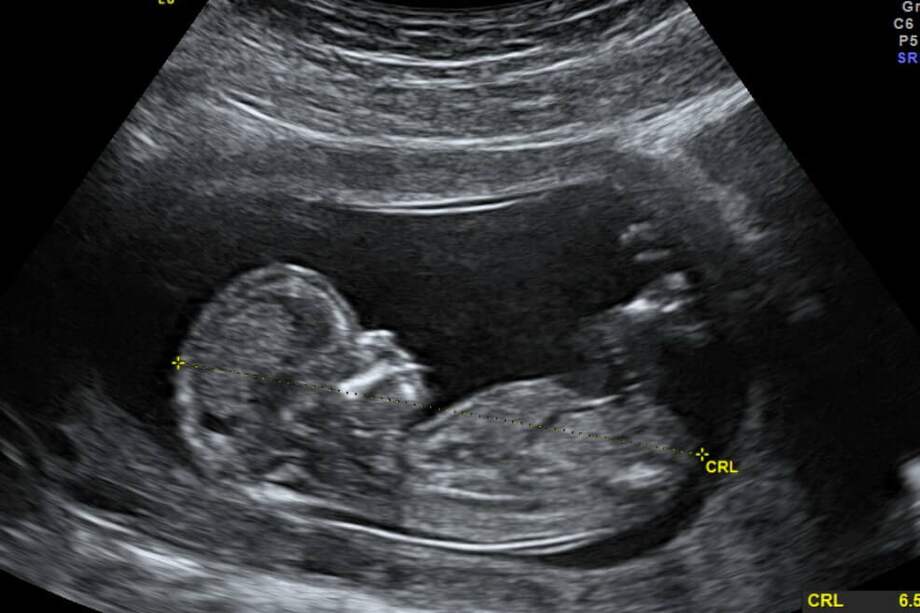

En el caso de Itzamara los cirujanos tuvieron que hacer una doble cesárea. La primera a su madre, a las 37 semanas de embarazo. La segunda, a la bebé para extraer el feto que se alojaba en su vientre. Se trataba de un cuerpo sin corazón ni cerebro que estaba rodeado de líquido amniótico y se alimentaba a través de un cordón umbilical que provenía de su hermana.